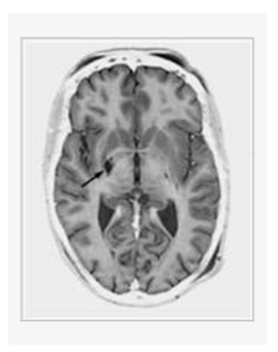

Of the following, which symptom, associated with advanced Parkinson disease and/or its long-term medical treatment, is most reliably controlled by the therapeutic lesion depicted in the magnetic resonance image shown in Figure 1?

a. Levodopa-induced dyskinesia

The patient whose magnetic resonance image is shown in Figure 1 most likely underwent surgery to control which of the following symptoms associated with which disease: a. Levodopa-induced dyskinesia associated with Parkinson disease b. Torticollis associated with cervical dystonia. c. Rigidity associated with Parkinson disease. d. Akinesia associated with Parkinson disease. e. Tremor associated with Essential Tremor.

e. Tremor associated with Essential Tremor.